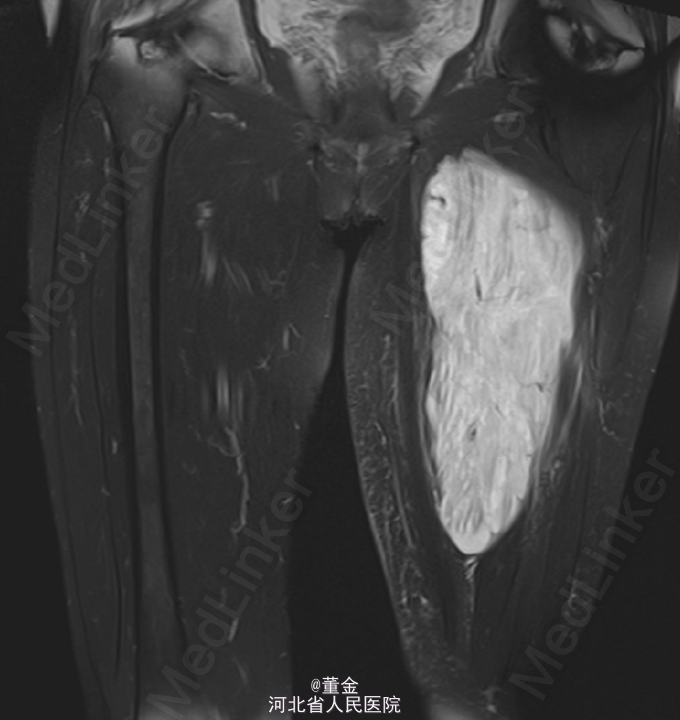

患者,女,72岁,因“发现左大腿内侧肿物伴逐渐增大3月余”入院。

左大腿内侧可见大面积肿块,质硬,活动可,无压痛,表面皮肤无破溃。四肢末端麻木感,末梢血供正常,病理征未引出。MR1.左大腿肌间隙恶性肿瘤,平滑肌肉瘤可能性大,神经鞘瘤恶变待排。2.左股骨下段内固定术后。DR:腰椎内固定术后改变.

初步诊断:1.左大腿内侧软组织恶性肿瘤. 全麻下行“左大腿软组织肿瘤切除术”,术中见肿瘤大小约25*15*10cm,肿瘤质软,边界不清,肿瘤周围水肿明显,予完整切除肿瘤。